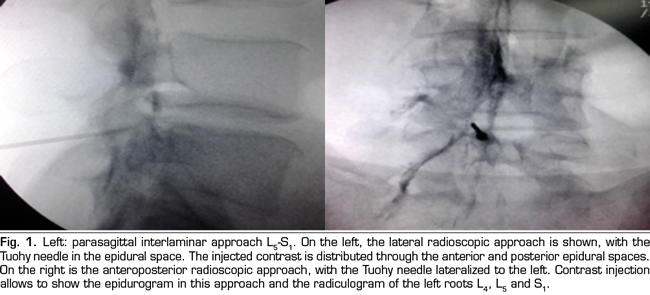

The procedure was performed in the surgical room. A peripheral venous catheter was placed with the patient on ventral decubitus position. Asepsis was conducted with alcoholic chlorhexidine and the local anesthesia was performed with 0.5 % lidocaine. Eighteen 3 1/2 or 4 3/4 inches tuohy needles (depending on patient size) were used for the parasagittal interlaminar technique. In the anteroposterior radioscopic view, the needle was inserted into the L4-5 or L5-S1 interlaminar spaces, using the tunnel vision technique, homolateral parasagittal of the side corresponding to the radicular pain (Figure 1). Loss of resistance was performed with saline. In the lateral view, a 4 mL contrast injection (Omnipaque©) was administered and the presence of anterior, posterior or both epidurograms was recorded (Figure 1). In the anteroposterior view the presence of radiculogram was recorded (Figure 1). A vial of betamethasone (12 mg of a mixture of phosphate and betamethasone acetate in 2 mL of solution) was then administered diluted with 3 mL of 0.5% lidocaine (total solution: 5 mL). The technical quality of the procedure was determined with the presence of paresthesia or concordant pain during the injection, and radiological data such as presence of radiculogram (Figure 1). Twenty two, 3 1/2 or 4 3/4 inches quincke needles were used in the transforaminal group and inserted using the oblique, lateral and anteroposterior radiological views.

The technical quality of the epidural steroid injection was evaluated in 21 out of 26 procedures performed with the parasagittal interlaminar approach. Anterior epidurograms, that is, achievement of the solution on the ventral epidural space, was obtained in 15 (71 %) of the patients (Figure 1 left); 17 (85 %) patients referred pain or paresthesia in the radicular territory during the injection, and a radiculogram was found in 12 (60 %) patients.